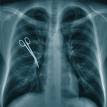

As hard as it is to believe, surgeons and surgical teams sometimes leave stuff in their patients.

You name it. If it is involved in surgery, it has probably been accidentally left inside someone.

As you can imagine however, your body isn’t going to easily accept these foreign bodies, and complications occur – infection, sepsis, gangrene.